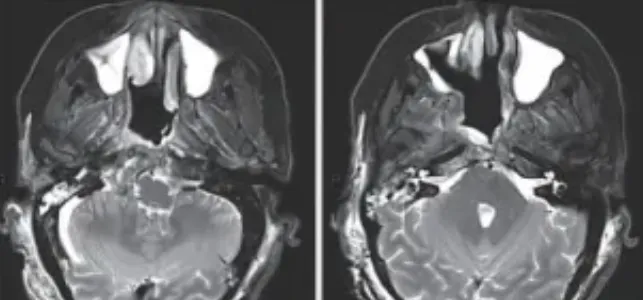

▼第二阶段开颅手术结束,嵴索瘤基本被完全切除。